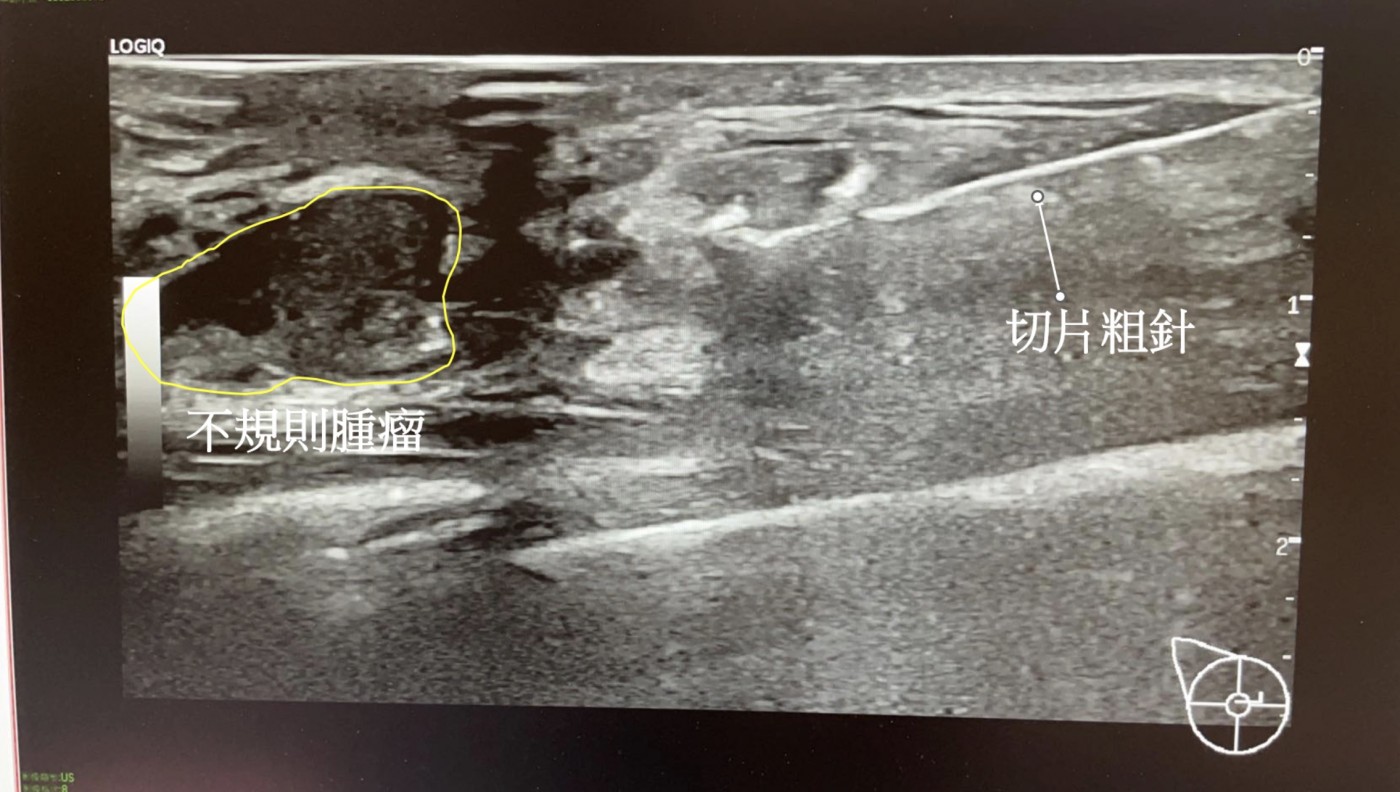

1. 超音波定位腫瘤

確認要進針的位置。

3. 粗針穿刺取樣

利用超音波導引進針,連續取 2–3 塊組織。

患者通常只會聽到「啪」的一聲,但不會疼痛。

- 形狀不規則、邊界不清楚

- 高大於寬(taller-than-wide)

- 低回音且內部異質